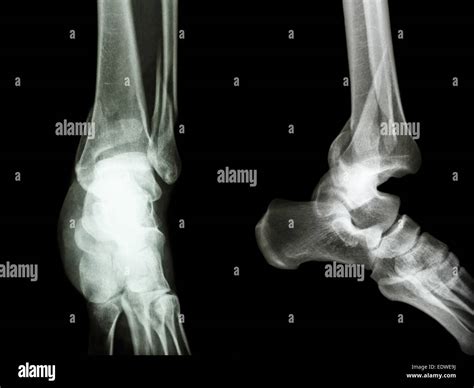

Diagnosing a displacement bone fracture typically involves a combination of physical examination and imaging tests. The diagnostic process usually includes:

• Physical examination: A healthcare provider will assess the injured area for pain, swelling, deformity, and loss of function.

• X-rays: These are the primary imaging tool used to visualize the bone and determine the extent of the fracture and displacement.

• CT scans: For more detailed images, especially in complex fractures, a CT scan may be ordered.

• MRI scans: These can provide information about soft tissue damage and are sometimes used in conjunction with X-rays and CT scans.